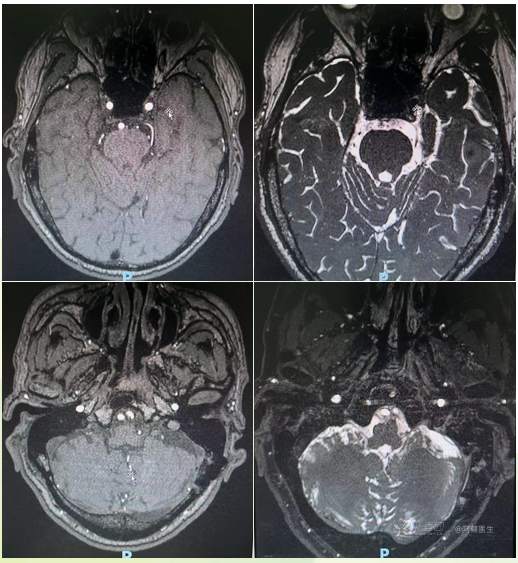

我院三叉神经/面神经MRI(第二次手术前)

MR:左侧舌咽神经周围结构稍紊乱,似见原小脑后下动已移位,未见明确血管压迫;左三叉神经似与血管(小脑上动脉)关系密切(医师自己阅片)